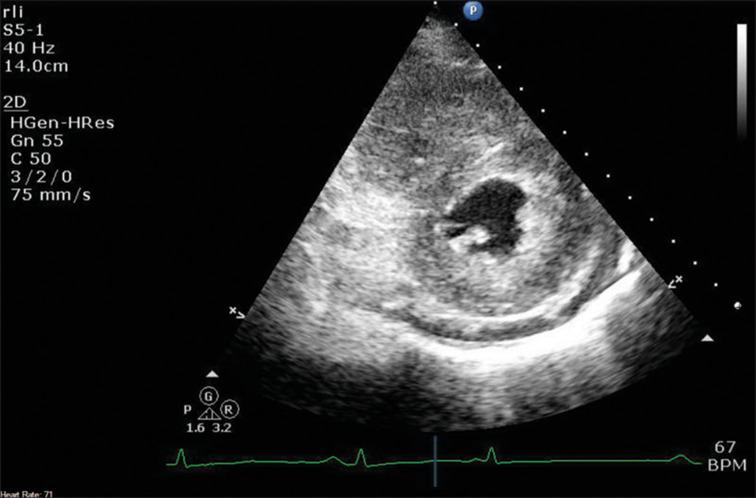

Loeffler first described "fibroplastic parietal endocarditis with blood eosinophilia" in 1936. This we now know refers to the most common cardiac manifestation of an uncommon condition, the so-called hypereosinophilic syndromes. This condition typically results in a restrictive cardiomyopathy affecting the left heart, but here, we present an unusual case of a 65-year-old woman with chronic hypereosinophilia of at least 2 years, who presented with right heart failure as a result of eosinophilic endomyocardial infiltration of her right ventricle. We explore the diagnostic pathway and look at the literature on management.

勒夫勒于1936年首次描述了“伴有血液嗜酸性粒细胞增多的纤维增生性心内膜炎”。我们现在知道,这指的是一种罕见病症(即所谓的嗜酸性粒细胞增多综合征)最常见的心脏表现。这种病症通常会导致影响左心的限制性心肌病,但在此,我们报告一例不寻常的病例,一名65岁女性,患有至少2年的慢性嗜酸性粒细胞增多症,因右心室嗜酸性粒细胞性心肌内膜浸润而出现右心衰竭。我们探讨了诊断途径并查阅了有关治疗的文献。